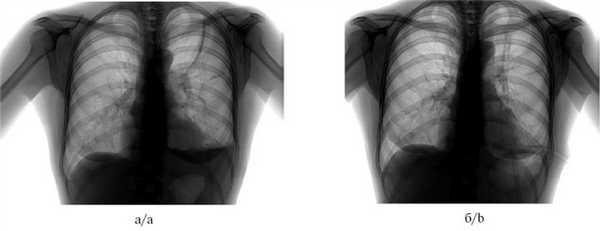

Рис. 2. Рентгенограммы органов грудной клетки пациента до (а) и после (б) выполнения окклюзии бронха.

а — пневмоторакс слева, подкожная эмфизема левой половины грудной клетки, б — через 2 сут после окклюзии, пневмоторакс разрешен, подкожная эмфизема не определяется.